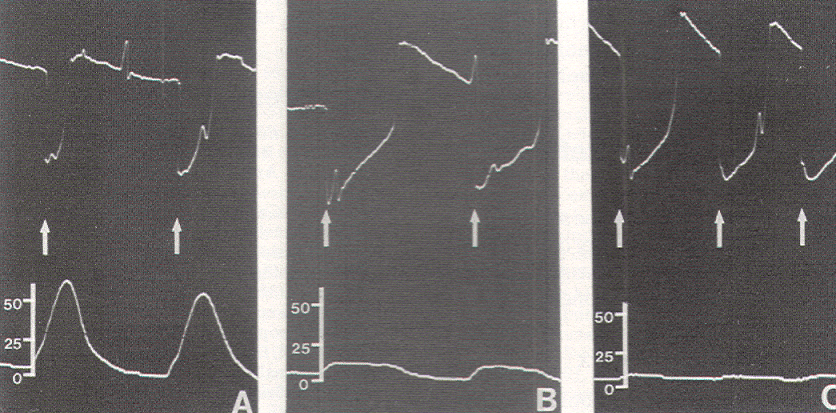

Figure 8. Use of the EGG. A) Stimulation of a

nonfunctional element (fibrous adhesion band) showing

only EGG stimulus artifacts (arrows) but no pressure

response. Scale in torr. B) Recognition of a faulty

nerve stimulator when neither an EGG stimulus artifact

nor a pressure response is detectable. Scale in torr. |